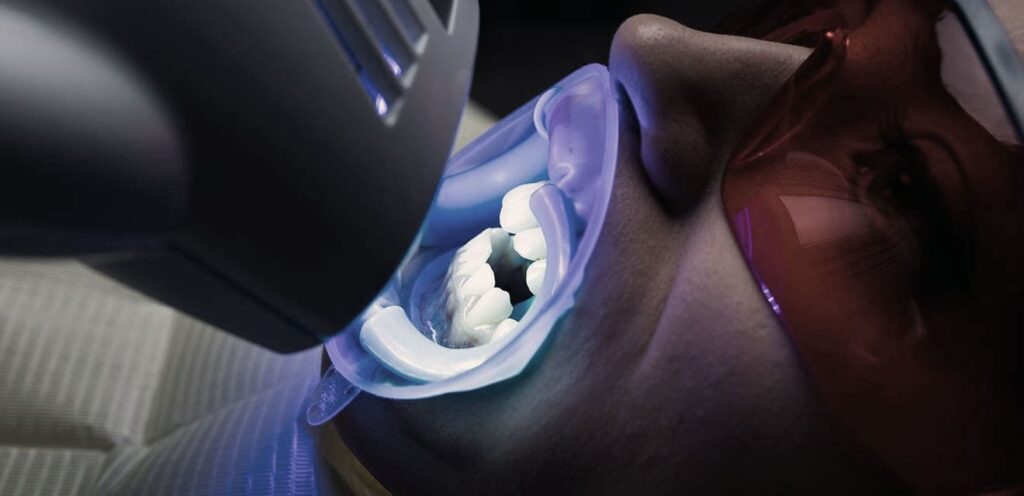

Diş Beyazlatma

Estetik Diş Hekimliği Diş Beyazlatma Nedir? Estetik bir gülüşe sahip olmak isteyen herkes için en önemli noktalardan biri dişlerin rengidir. Işıl ışıl parlayan beyaz dişler hem sağlıklı bir gülümsemenin hem de kendine olan güvenin altını çizmektedir. Dişlerin genetik faktörlere bağlı doğuştan gelen bir rengi vardır. Nasıl ki kişilerin ten rengi varsa diş rengi de kişiden […]